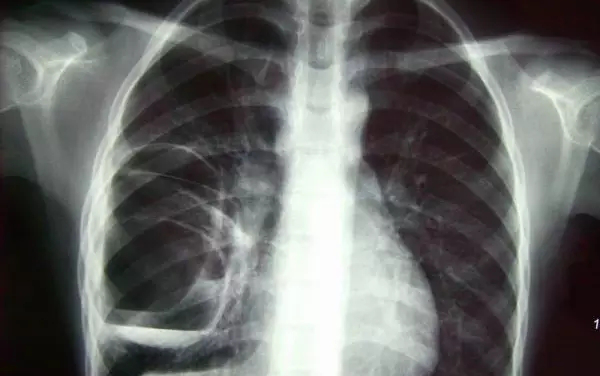

3、胸部——粗看X光平片,細(xì)看CT

X光胸片可粗略檢查肺、心影、主動脈弓、肋骨等,可以檢查有無肺紋理增多、肺內(nèi)較大腫塊、主動脈結(jié)鈣化等。胸部CT檢查顯示出的結(jié)構(gòu)更清晰,對胸部病變檢出敏感性和準(zhǔn)確性均優(yōu)于常規(guī)X光胸片,特別是對于篩查早期肺癌有重大意義。而磁共振成像對于肺內(nèi)疾病的診斷,應(yīng)用非常有限。